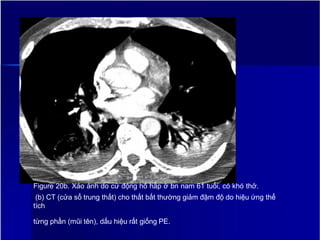

Figure 20a. Xảo ảnh do cử động hô hấp ở bn nam 61 tuổi, có khó thở.

Figure 20b. Xảo ảnh do cử động hô hấp ở bn nam 61 tuổi, có khó thở.

(b) CT (cửa sổ trung thất) cho thất bất thường giảm đậm độ do hiệu ứng thể

tích

từng phần (mũi tên), dấu hiệu rất giống PE.